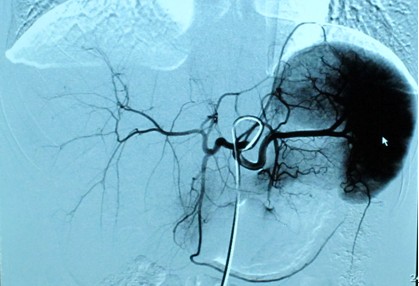

干疗三科徐勉主任和柯亭羽医生多年来一直从事干细胞基础和应用的研究工作,为了做好这次治疗,又参考了国内外医院干细胞治疗糖尿病的经验,决定采用脐血干细胞通过胰背动脉介入的方式进行移植。征得患者及家属同意后实施了手术,过程非常顺利,一个小时就完成了治疗。